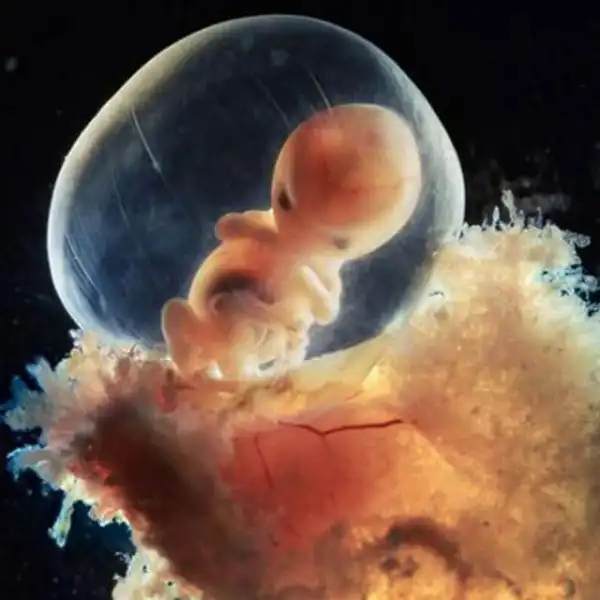

40 дней. Наружные клетки зародыша срослись с рыхлой поверхностью матки и образуют плаценту, или детское место. Это губчатый кусок плоти служит человеку в первые девять месяцев его жизни и легкими, и желудком, и печенью, и почкой...

Восемь недель. Быстрорастущий эмбрион хорошо защищен во чреве матери. С помощью электронного микроскопа Нильссон смог увеличить изображение в сотни тысяч раз.